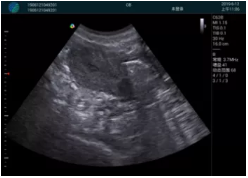

肝內(nèi)血管顯示清晰,血流敏感無外溢